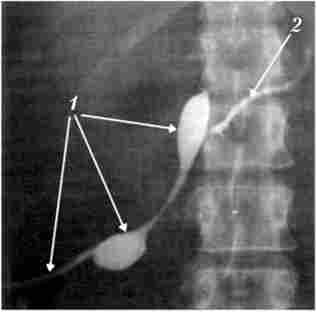

Мал. 20.21. Фістулограмма.

Зовнішній бічній свищ підшлункової залози:

1 - в свищевой хід введена трубка; 2 - панкреатичний протік простежується на всьому протязі, і контрастну речовину вільно проходить в дванадцятипалу кишку